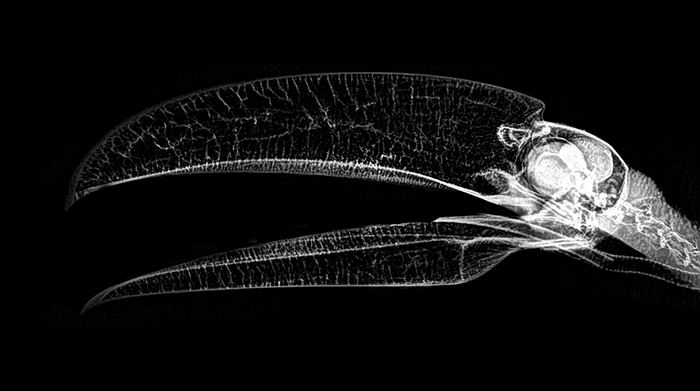

9. นกทูแคนอกขาว (Toco Toucan)